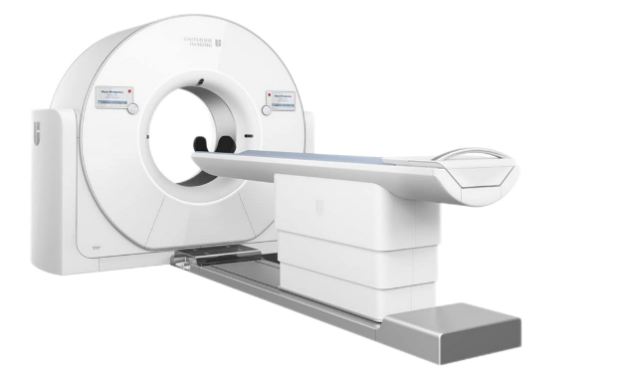

联影uCT960+

近日

搭载320排640层的超高端CT

在奉贤区中心医院放射医学科

成功装机试运行